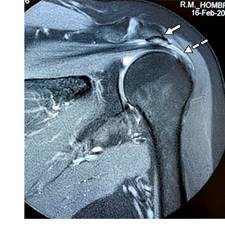

Se trata de paciente femenino de 69 con dolor en el hombro izquierdo de seis meses de evolución, principalmente con movimientos de abducción y flexión de codo. A la exploración de hombro izquierdo: arcos de movimiento limitados en abducción a 90o por dolor al igual que rotación externa de 45o, a la palpación masa dolorosa de aproximadamente 2 cm en borde interno del tendón de la porción larga del bíceps por debajo de la corredera bicipital. Prueba de choque de Neer, Hawkins y prueba de Yergason positivas; pruebas de inestabilidad de la articulación glenohumeral negativas. Las radiografías simples no mostraron hallazgos anormales. La resonancia magnética mostró: tendinosis del supraespinoso con ruptura parcial en su inserción, además de acromion tipo III con osteofitos subacromiales causantes de pinzamiento (Figura 1); en ponderación T2 se encontró tendinopatía de la porción larga del bíceps braquial con incremento de líquido en la corredera bicipital y quiste sinovial en su tercio proximal de 2.0 × 1.4 × 1.2 cm, con apariencia de estar encapsulada por la vaina del tendón bicipital (Figuras 2 y 3). Se canalizó a cirugía articular.

Figura 1: Imagen de resonancia magnética ponderada en T2, en corte coronal. Se muestra acromion tipo III, osteofitos subacromiales (flecha) y tendinosis y ruptura parcial del tendón supraespinoso a nivel de su inserción (flecha punteada).

La resonancia magnética es la modalidad de imagen más adecuada para la evaluación de lesiones quísticas articulares o yuxtaarticulares; la mayoría de las lesiones quísticas muestran un patrón típico de intensidad de señal de líquido, a su vez deben evaluarse las anomalías articulares asociadas que incluyen, como en este caso, tendinosis y desgarro del supraespinoso y el síndrome de pinzamiento ocasionando por un acromion tipo III para su corrección quirúrgica.3